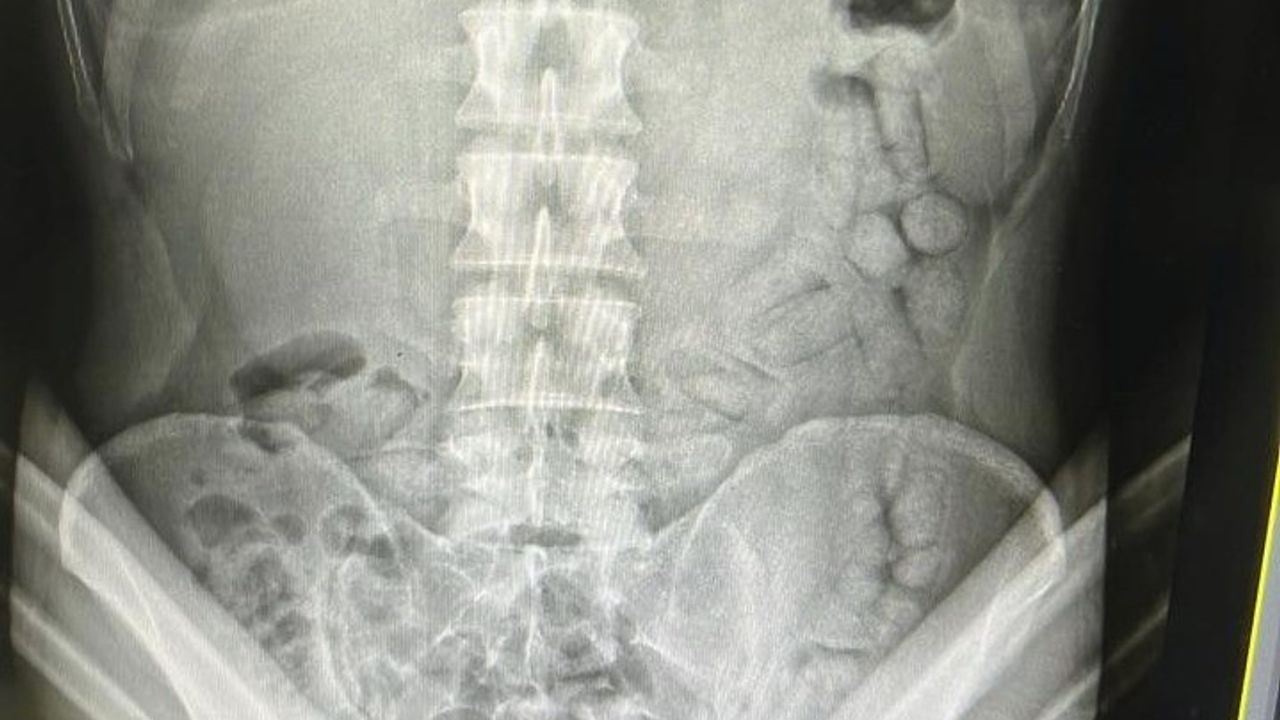

Adli makamların talimatı üzerine Gümüşhane Devlet Hastanesine götürülen şahsa yönelik iç beden muayenesinde bağırsaklarında 55 adet kapsül olduğu tespit edildi. Hastanede yapılan müdahalenin ardından şahsın bağırsaklarından çıkarılan kapsüllerin içerisinde toplamda 317,46 gram metamfetamin ele geçirildi. Hakkında Uyuşturucu Madde Nakli suçundan işlem başlatılan yabancı uyruklu şahıs yasal işlemlerinin tamamlanmasının ardından çıkarıldığı mahkemece tutuklanarak Gümüşhane E Tipi Kapalı Ceza İnfaz Kurumuna gönderildi.